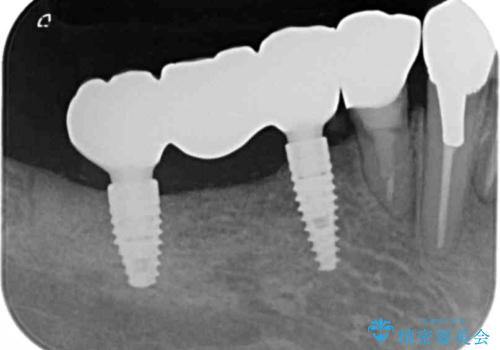

狭小な歯槽骨に対するインプラント治療

- 歯を失い噛めないこと、骨の幅が狭く他院でインプラント治療が難しいと断られ、当院でのインプラント治療が可能かどうか相談来院されました。

骨の造成、角化歯肉の移植を行いインプラント周囲の環境を整えた治療を計画します。